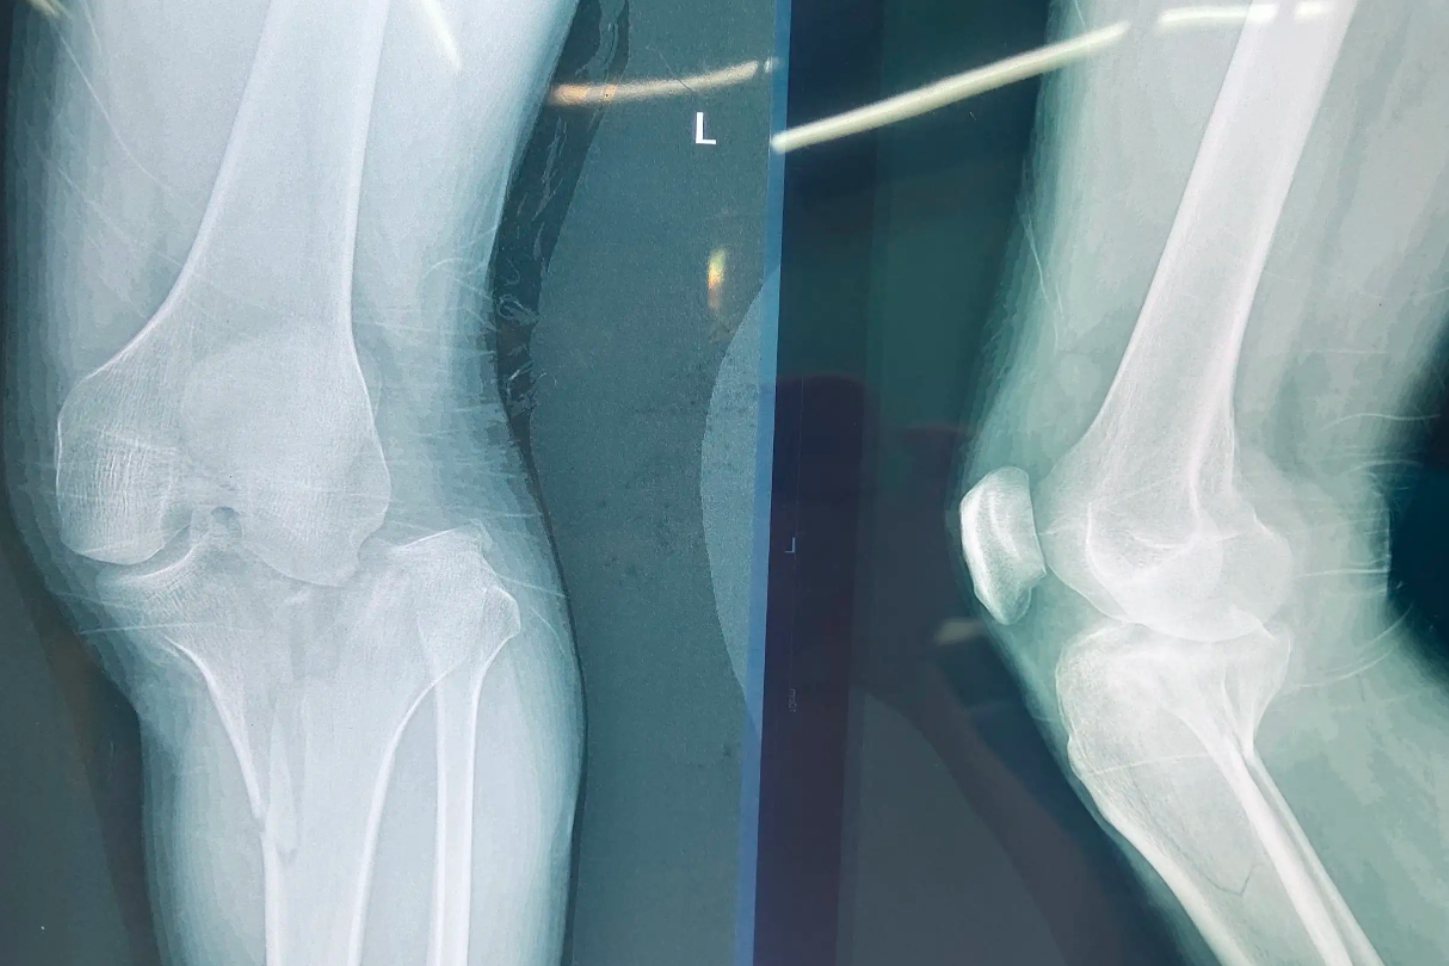

胫骨外旋的患者表现为站立双足并齐朝前时,两侧髌骨旋向外侧。行走时双足外旋,足尖指向外侧,呈外八字步态,容易绊倒。严重者外旋达90°,并呈扁平足。胫骨外旋患者常主诉膝关节前方疼痛、易疲劳。

胫骨外旋使用支具矫正效果不理想,轻症多数采用观察治疗和对家长进行宣教。中度到重度畸形者,需要警惕脑瘫的可能性,8岁以上的患者外旋畸形超过30°时才有旋转截骨术的指征。